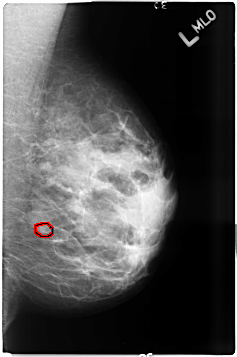

ics_version 1.0 filename B-3497-1 DATE_OF_STUDY 20 5 1998 PATIENT_AGE 38 FILM FILM_TYPE REGULAR DENSITY 3 DATE_DIGITIZED 8 6 1999 DIGITIZER LUMISYS LASER SEQUENCE LEFT_CC LINES 4624 PIXELS_PER_LINE 3056 BITS_PER_PIXEL 12 RESOLUTION 50 OVERLAY LEFT_MLO LINES 4640 PIXELS_PER_LINE 3072 BITS_PER_PIXEL 12 RESOLUTION 50 OVERLAY RIGHT_CC LINES 4600 PIXELS_PER_LINE 3032 BITS_PER_PIXEL 12 RESOLUTION 50 NON_OVERLAY RIGHT_MLO LINES 4600 PIXELS_PER_LINE 3008 BITS_PER_PIXEL 12 RESOLUTION 50 NON_OVERLAY |

FILE: B_3497_1.LEFT_MLO.OVERLAY TOTAL_ABNORMALITIES 1 ABNORMALITY 1 LESION_TYPE CALCIFICATION TYPE PLEOMORPHIC DISTRIBUTION CLUSTERED ASSESSMENT 4 SUBTLETY 3 PATHOLOGY BENIGN TOTAL_OUTLINES 1 BOUNDARY |